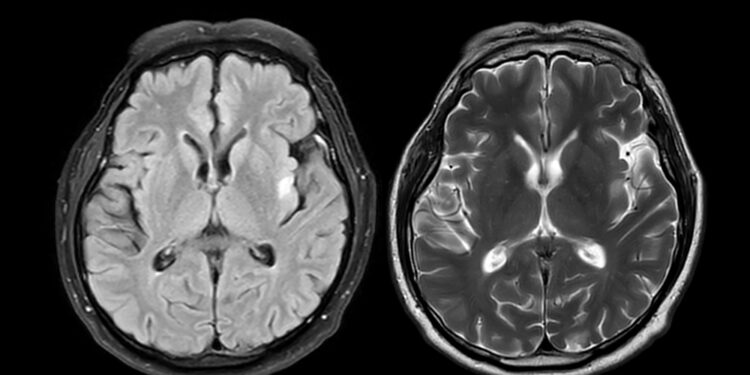

- Smegenų magnetinio rezonanso tomografija (MRT) padeda įvertinti mielino netekimo židinius, būdingus MLD.